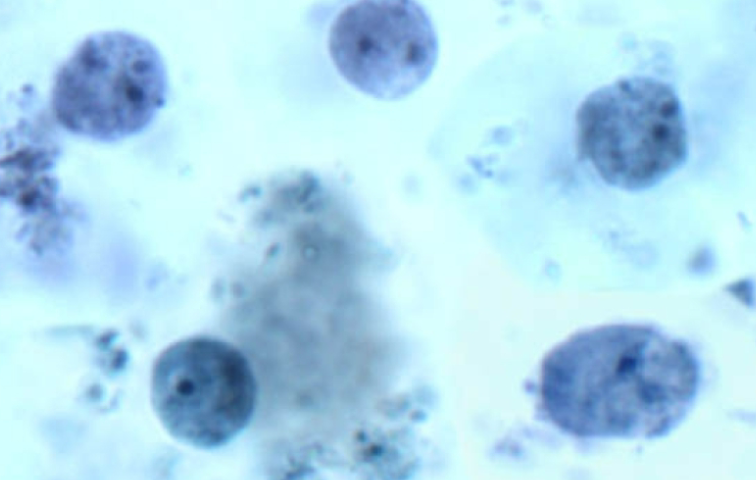

Balantidum coli Cyst